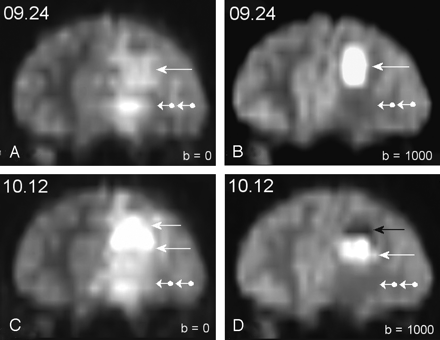

A few years ago, we published the observation of a 14-year-old boy presenting with a pyogenic frontal brain abscess brain that was not immediately treated surgically and showed two components that evolved with time on serial DW images (3). Newly reformatted images of this case are shown in Figures 1 and 2. The patient presented with a febrile meningeal syndrome and biologic markers for sepsis. We observed a strong time dependence of both signal intensity and apparent diffusion coefficient (ADC) values of the abscess throughout serial DW image monitoring. In the initial phase of the disease course a hyperintense material completely filled the abscess cavity, in which the ADC was decreased when compared with contralateral normal brain tissue (Figs 1A, 2B). The strong hyperintensity in the homogeneous core was thus far prominently due to true diffusion-weighting because only moderate hypersignal intensity was observed on corresponding T2-weighted images (Fig 2A). Shortly after the initiation of empirical antibiotic therapy, a sharply delineated hypo-/hyperintense interface between pus sediment and fluid supernatant appeared (Fig 1B). The ADC values of the hyperintense component had then become slightly elevated when compared with normal brain tissue, thereby suggesting the prominence of the T2-weighted shine-through effect in the hyperintensity of the lesion (Fig 2D). Delayed stereotactic drainage confirmed the presence of thick pus containing neutrophilic pyocytes but failed to identify the causative organism. A second follow-up examination after drainage revealed further shrinking of the hyperintense component (Fig 1C).

Patient 1. T2-weighted shine-through effect in the hyperintense component.

A and B, Status at admission. A, Frontal reformat of the T2-W image of the echo-planar imaging (EPI)–spin-echo (SE)–DW sequence with b factor = 0. Left frontal parenchyma displayed hyperintensity. Inferior area (double-ball arrowhead) seemed very slightly brighter than the superior one (arrow). B, Similar image after application of the diffusion-sensitizing gradients at b factor = 1000 s/mm2. The inferior area became hypointense and corresponded to vasogenic interstitial edema with mean ADC values at 1480 mm2/s. Superior area remained hyperintense because of prominent diffusion-weighting effect with a mean ADC at 650. Mean ADC was 780 in the contralateral normal brain tissue.

C and D, Status at 3 weeks. C, Frontal reformat of the T2-weighted image of the EPI-SE-DW sequence (b = 0). Left frontal parenchyma is still hyperintense, with little change when compared with panel A, except for more perceptible hyperintensity within superior areas (arrows) when compared to inferior areas (double-ball arrowhead). D, Similar image after application of the diffusion-sensitizing gradients at b = 1000. Inferior area of vasogenic edema displayed similar hypointensity as on admission (see panel B). A sharply delineated interface has appeared within the superior area separating a very hypointense upper area (black arrow) in which mean ADC value was measured at 2320 and a lower one (white arrow) with persistent hyperintensity in which mean ADC value was 1130. The upper area corresponded to fluid supernatant and the lower area to shrinking purulent core in which fibrinolysis has decreased the restriction to the water diffusion within pus when compared with the initial status (see panel B). The T2-weighted shine-through effect was thus far mainly responsible for hyperintensity in this subarea, and not the true diffusion weighting effect.